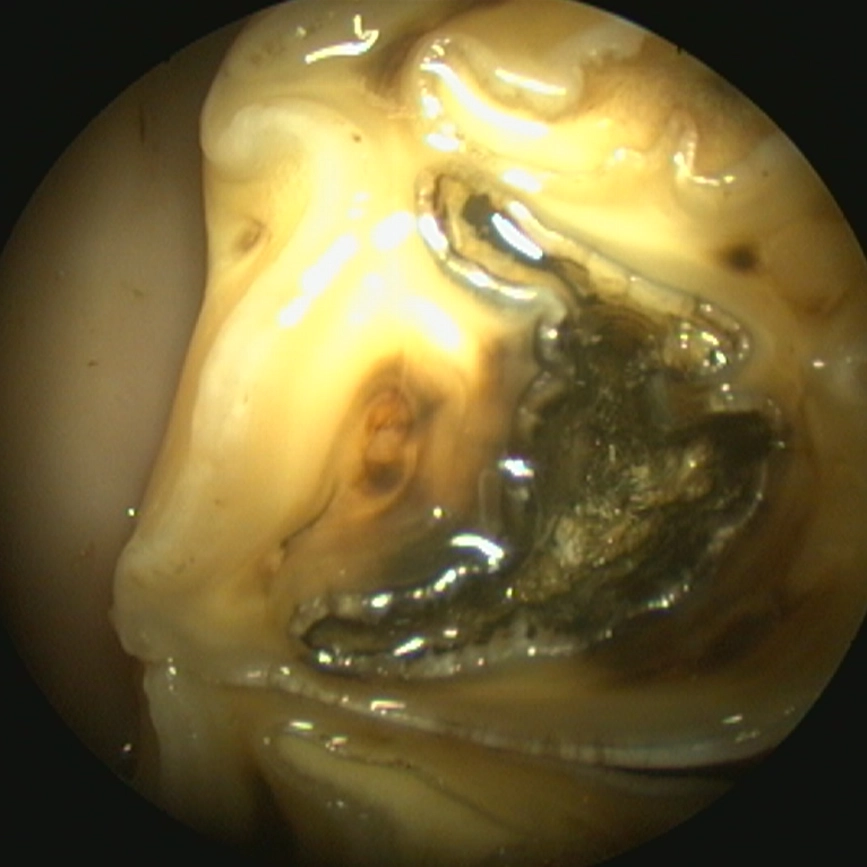

Caries filling